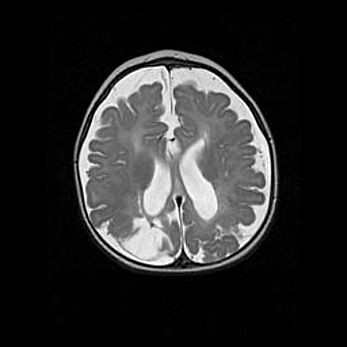

Церебральная ишемия II.

Возраст: 5 дней

Вес: 3400 г

Пол: женский

Окружность головы: 35 см

Срок гестации: 39 недель

Церебральная ишемия – это заболевание, характеризующееся недостаточностью (гипоксией) либо полным прекращением (аноксией) снабжения мозга кислородом по причине закупорки одного или нескольких сосудов. Это приводит к  что метаболическим расстройствам различной степени тяжести в тканях головного мозга, развитию коагуляционных некрозов и гибели нейронов.